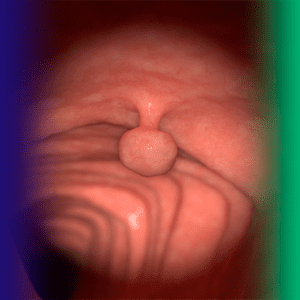

Pólipos do cólon: visão geral do distúrbio digestivo

A maioria dos cânceres colorretais se origina a partir de pólipos. Identificá-los, classificá-los e decidir o manejo correto é uma…